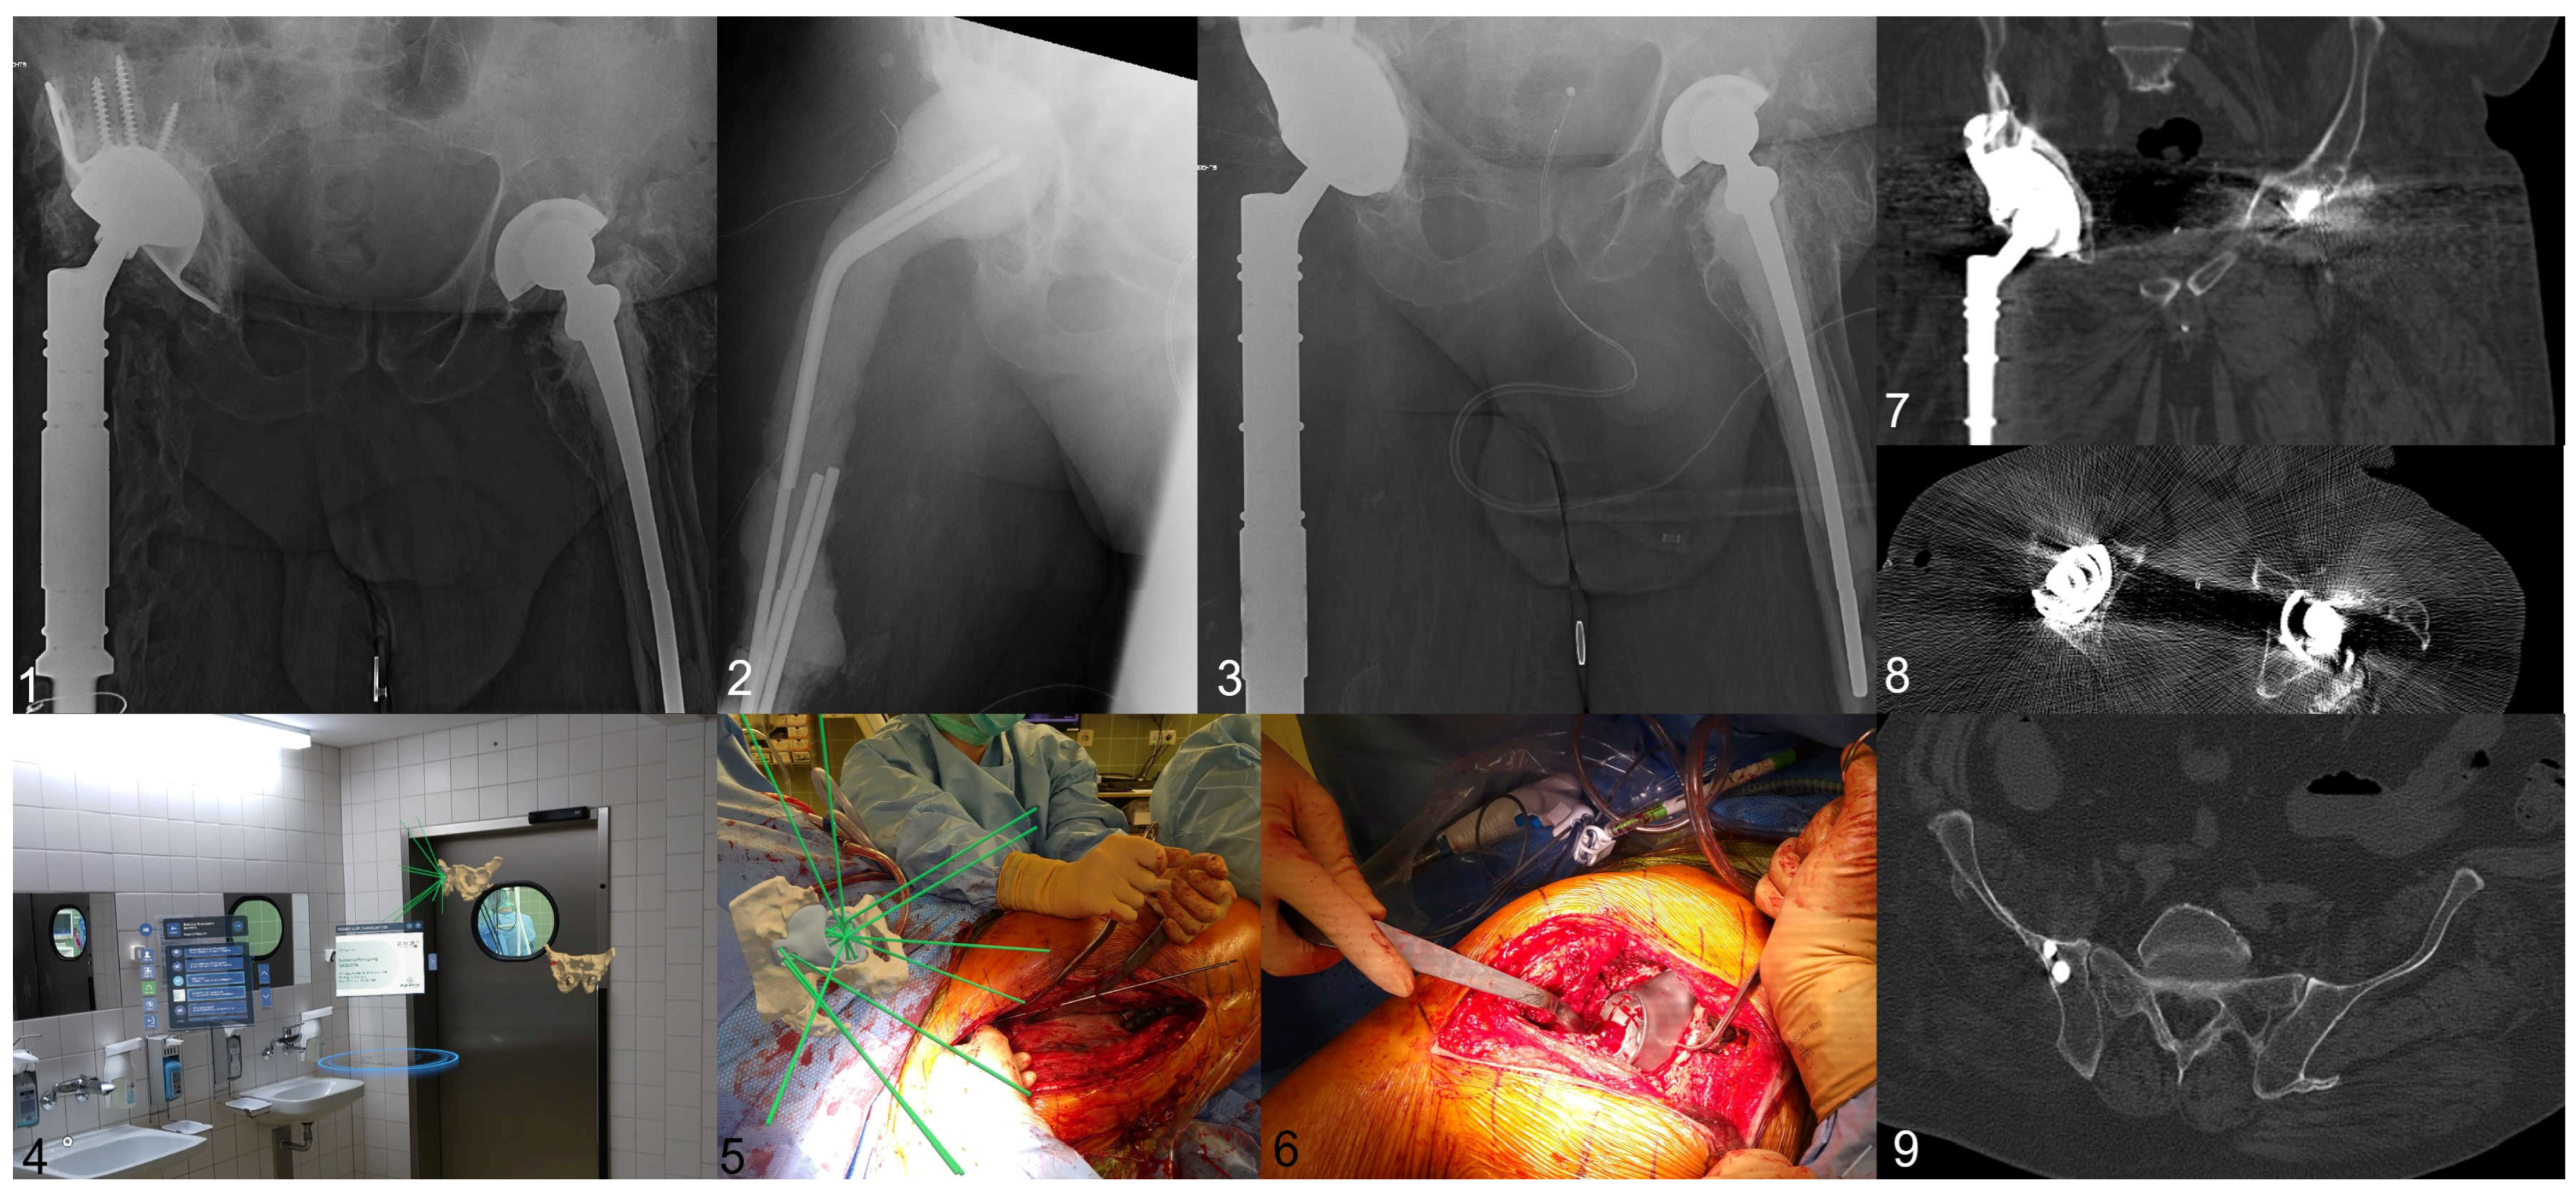

Implementation of an Intraoperative Augmented Reality Environment for Custom-Made Partial Pelvis Replacements—A Proof of Concept and Initial Results

5. Results

6. Personal Experience and Workflow